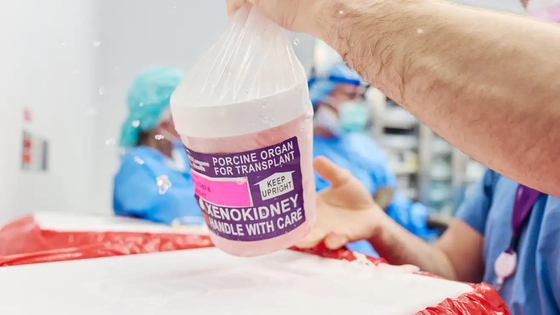

Óriási orvosi siker: két hónapja él génmódosított sertésvesével egy amerikai nő, és jól érzi magát

Áttörést jelenthet a xenotranszplantációban annak az amerikai nőnek az esete, akit még 2024 novemberében műtöttek meg New Yorkban, hogy génmódosított sertésvesét kapjon. Hamarosan Alabamába is hazatérhet.